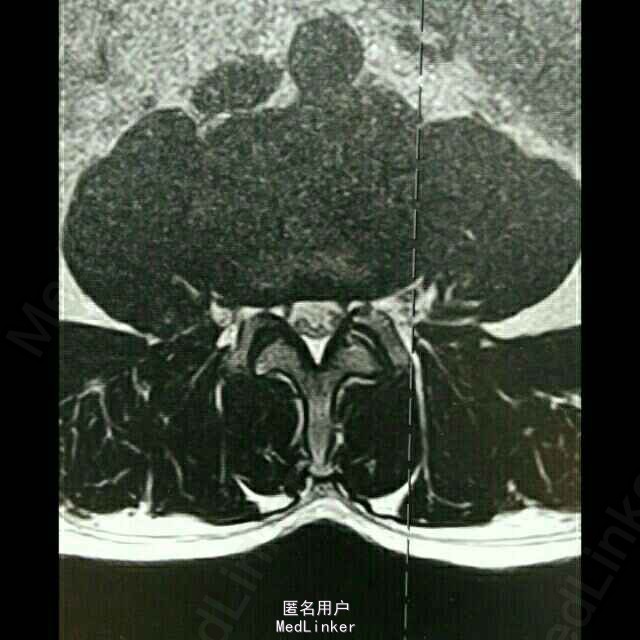

患者,男,59岁。20天前,患者无明显诱因出现右腿麻木,时有头晕、头痛、恶心等症状,亦未做过任何治疗,经休息后上述症状可缓解;在此期间,右下肢麻木逐渐加重,自觉行走无力。

脊柱序列如常,生理曲度存在,未见后凸及侧弯畸形。颈椎前屈、后伸、侧屈及旋转功能无明显受限,颈3-7椎间隙及棘突旁压痛。腰椎棘突及椎旁压痛,右小腿内侧皮肤感觉较左侧减退。